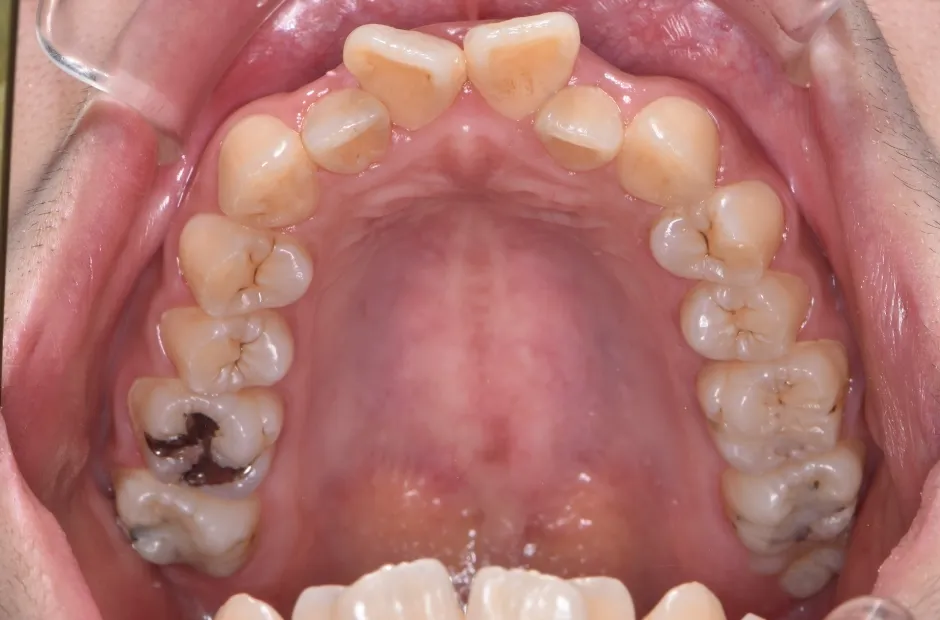

叢生

| 診断名・主訴 | 叢生 |

|---|---|

| 年齢・性別 | 43歳・女性 |

| 治療期間・回数 | 2年7か月 27回 |

| 治療に用いた主な装置 | 舌側矯正 |

| 抜歯部位 | 両顎4,4 |

| 治療費 | 100万円(税抜) |

| リスク・副作用 | 装置による違和感・疼痛・歯肉退縮・歯根吸収・虫歯のリスクなど |

治療前